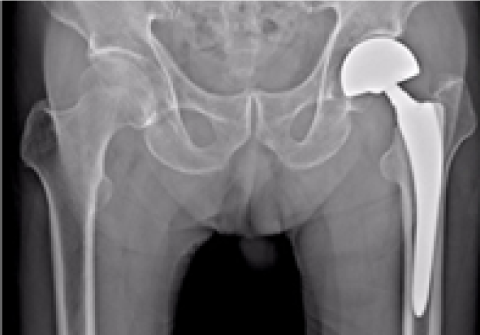

고관절 인공관절 전체치환술

2016.09.26

2017.01.24